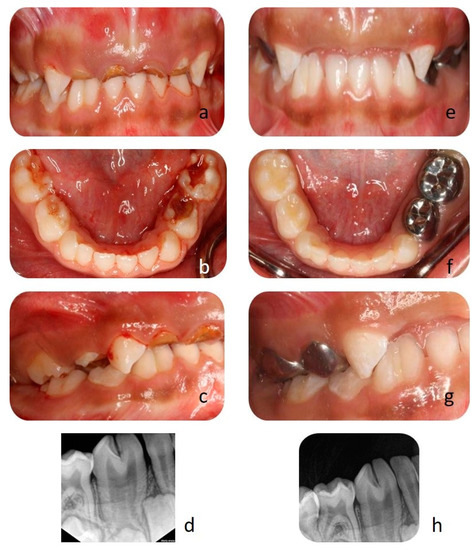

2. Case Report